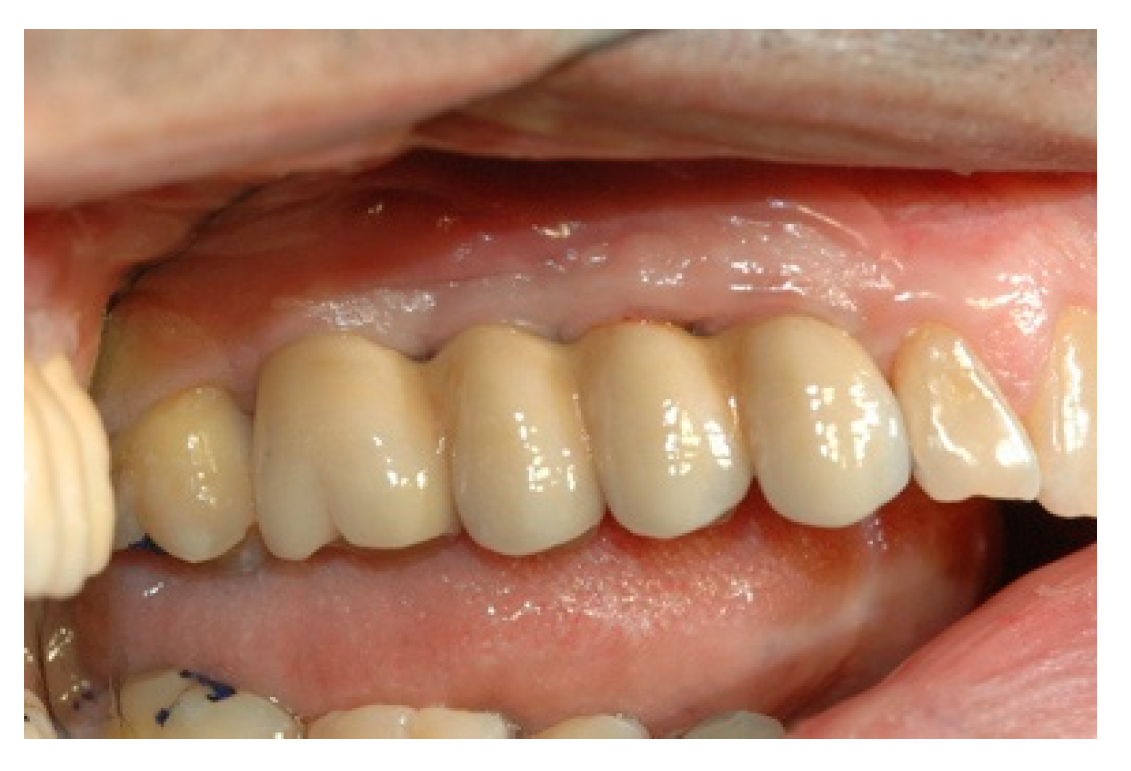

Once the mesostructure was made, it was checked to verify passive adaptation and its precise coupling with the arched fixtures (Figure 8 and Figure 9).

Upon positive feedback, the construction of a superstructure was carried out by performing fusion and subsequent ceramicization in the laboratory (Figure 10 and Figure 11).

Figure 10. The built superstructure.

Prosthesis 02 00023 g010

Figure 11. The built superstructure.